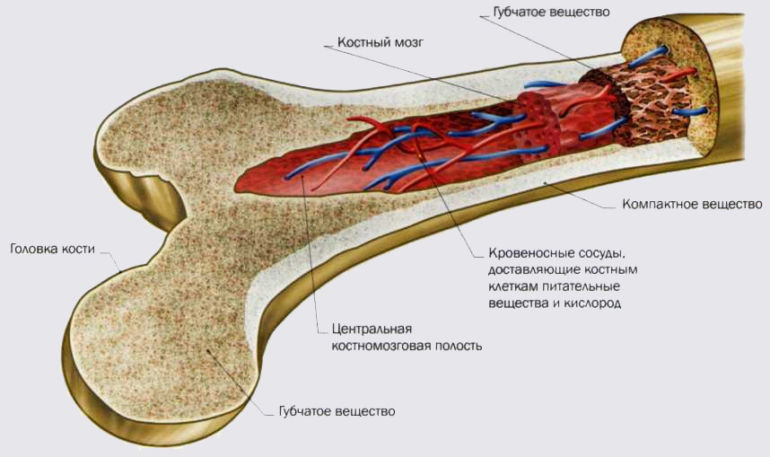

Скелет – это основа и опора любой части тела. В свою очередь, кость – орган, имеющий определенное строение, состоящий из нескольких тканей и выполняющий определенную функцию.

Каждая отдельно взятая кость (в том числе, кость руки человека) имеет:

Самое главное, каждая кость занимает строго определенное место в организме человека.

Кости в организме выполняет большое количество функций, такие как например: